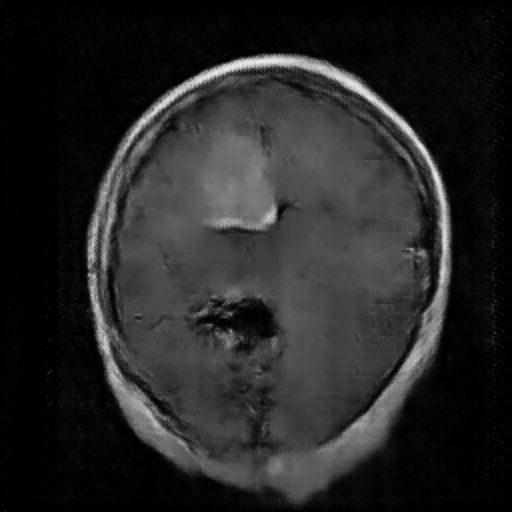

Figure 3. The Image Generated by DCGAN (Left one is no tumor).

In the image above, the right one is the image with meningioma generated by the DCGAN. We can see that there is a tumor at the upper left, which is kind of brighter. However, the complexity of the brain makes it hard for the model to learn and generate images very well. In this case, it’s not easy for the DCGAN to generate really similar images. Just like Figure 3, It rarely has the the detail for the brain compared with the original image, especially the image with meningioma. In the image with meningioma, it’s hard to find any texture or organ that should be contained in the brain. However, the CNN model may still learn from the images generated by the DCGAN by capturing specific features like lighter areas, and the CNN model has increased its accuracy.